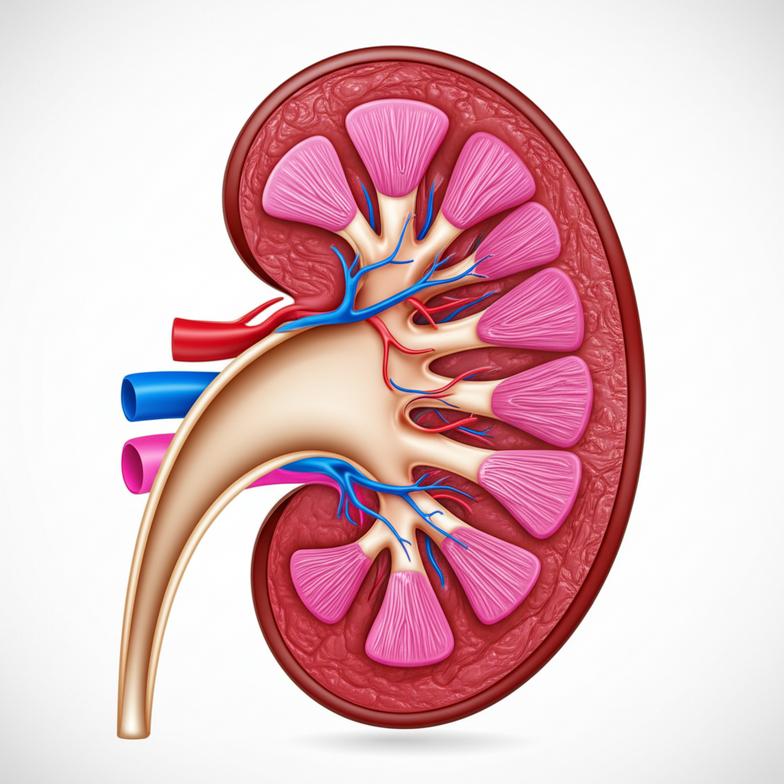

ไตเป็นอวัยวะที่มีหน้าที่สำคัญในการรักษาความสมดุลภายในร่างกาย ด้วยหน่วยกรองเล็กๆ นับล้านหน่วยที่เรียกว่า “เนฟรอน” ซึ่งทำหน้าที่กรองของเสีย ดูดซึมสารที่มีประโยชน์กลับคืน และรักษาระดับน้ำและเกลือแร่ให้เหมาะสม อย่างไรก็ตาม เมื่อเวลาผ่านไปหรือเมื่อต้องเผชิญกับปัจจัยคุกคามต่างๆ เนฟรอนเหล่านี้จะค่อยๆ เสื่อมสภาพและตายไป ทำให้ประสิทธิภาพการทำงานของไตลดลงเรื่อยๆ การเสื่อมของไตเป็นกระบวนการที่ซับซ้อน ไม่ได้เกิดจากสาเหตุเดียว แต่เป็นผลรวมจากปัจจัยหลายประการที่ทำงานร่วมกัน ได้แก่ ภาวะการอักเสบเรื้อรังในร่างกาย ความเครียดออกซิเดชัน (Oxidative Stress) ซึ่งเป็นภาวะที่เซลล์ถูกทำลายจากอนุมูลอิสระ รวมถึงภาวะหลอดเลือดผิดปกติที่ส่งผลให้เลือดไปเลี้ยงไตไม่เพียงพอ